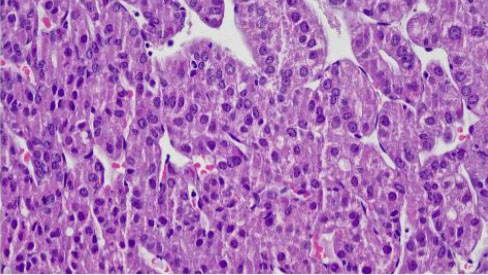

After discussion with the oncologist, a percutaneous biopsy of the right thigh mass was performed in July 2021. The histopathology examination (HPE) from the right thigh mass shows metastatic hepatocellular carcinoma. The malignant cells are positive for hepatocyte stain (Figure 1 and Figure 2). CD34 shows sinusoidal staining pattern (Figure 3 and Figure 4). His AFP at this time was 2.9 ng/mL. He was started on sorafenib but withheld in less than a month due to side effects of vomiting and diarrhea. Soon after discontinuation of the sorafenib he developed obstructive jaundice. Endoscopic retrograde cholangiopancreatography (ERCP) and stenting was done as a palliative intervention. The patient deteriorated and died within a month.

Figure 1: Tumor arranged in trabecular pattern intervened by thin-walled capillaries (H&E ×10).

Figure 2: The cells show mild to occasional moderate nuclear pleomorphism with vesicular nuclei and small nucleoli. The cytoplasm is abundant, granular, and eosinophilic (H&E ×40).